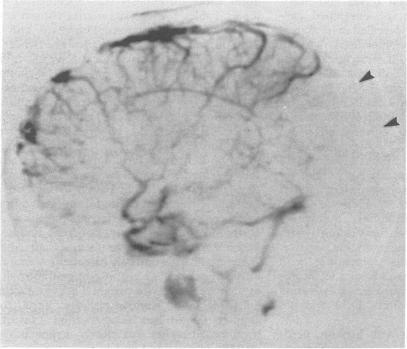

Behçet's disease is a multisystem disease characterised by the clinical triad of oral ulcers, genital ulcers and uveitis. Nervous system involvement is frequent and occasionally precedes other manifestations. Behcet's disease is not frequently considered in the differential diagnosis of papilloedema. We report four cases of Behcet's disease in which papilloedema occurred with or without dural sinus thrombosis. MRI is of great value in the investigation of such patients as it can demonstrate venous sinus thrombosis non-invasively or suggest the diagnosis by showing the associated parenchymal lesions secondary to small vessel pathology.